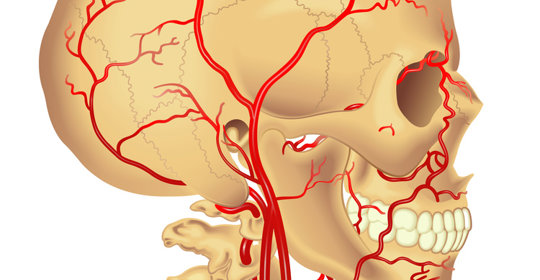

大腦與神經

腦外傷:症狀與處理方法

腦水腫:風險、治療與預防措施

腦水腫:處理方式與緊急性

腦外傷:症狀、處理與緊急醫療

腦積水:症狀、原因及處理方法

腦幹出血:顱內壓控制、生命支援、抗高血壓

腦幹出血:原因、症狀與治療

腦幹出血:原因與恢復

本文介紹了開顱手術後腦水腫的原因及恢復注意事項。

腦幹出血:前兆與應對

腦外傷:意識障礙、瞳孔異常、嘔吐、眩暈、呼吸不規則

腦幹出血:清醒機率與前兆

腦死:昏迷與聲音感知缺失

腦幹出血:後遺症、症狀及治療

腦幹出血:症狀、嚴重性與後遺症